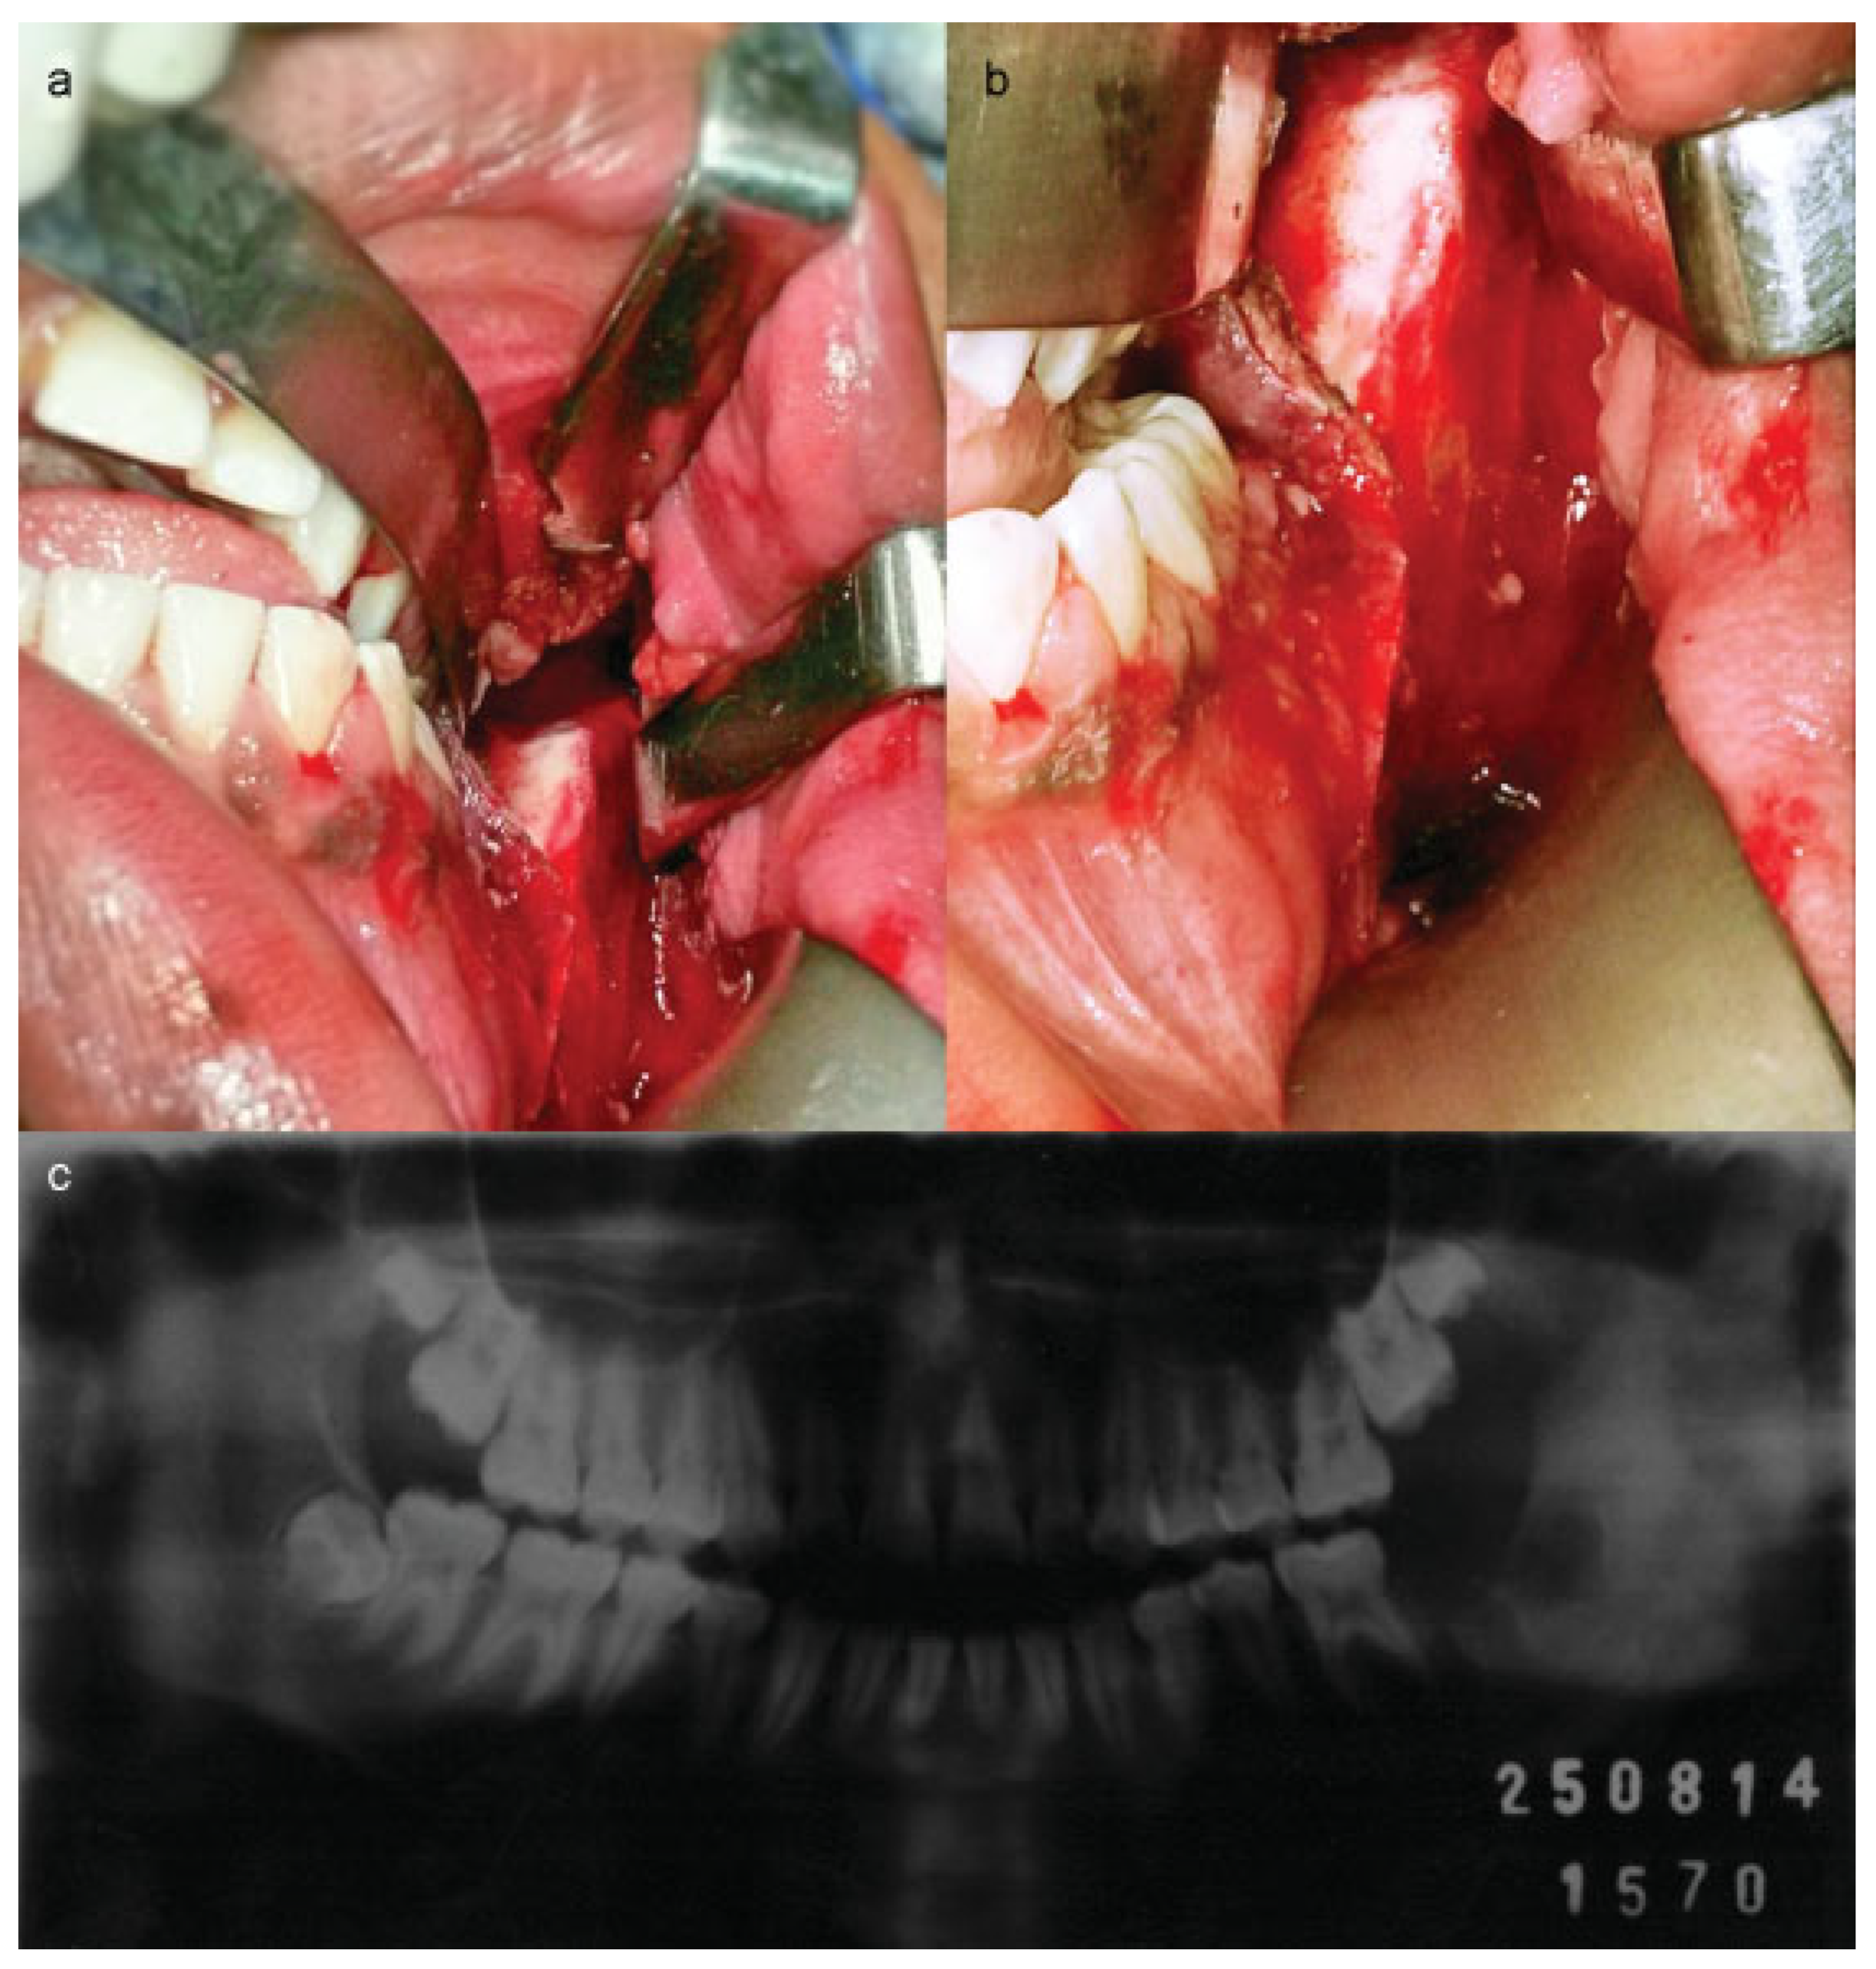

Surgical Treatment of Fibroosseous Lesion in Young Patient with Reduced Mouth Opening

:Case Report